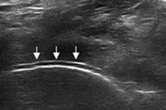

肌骨超声可通过高清影像图判定软骨表面有无出现一条与强回声骨皮质平行的线样强回声,即“双轨征”这一痛风性关节炎特征性表现,判定疾病所属。当尿酸盐粘附并沉积于漂浮的滑膜上时,超声检查可在关节腔内发现漂浮的高亮回声;而当尿酸盐长期沉积于韧带上时,在超声中即显示条带状的略高回声(韧带)中出现高回声点、高回声带或高回声团块(尿酸盐),从而判断痛风病情处于哪一时期。

“双轨征”

跖趾关节软骨表面可见高回声不规则增强的软骨滑膜边缘线,呈“双轨征”。

高回声带

软骨表面回声增强,与深面的骨性关节面强回声线形成“双轨征”。